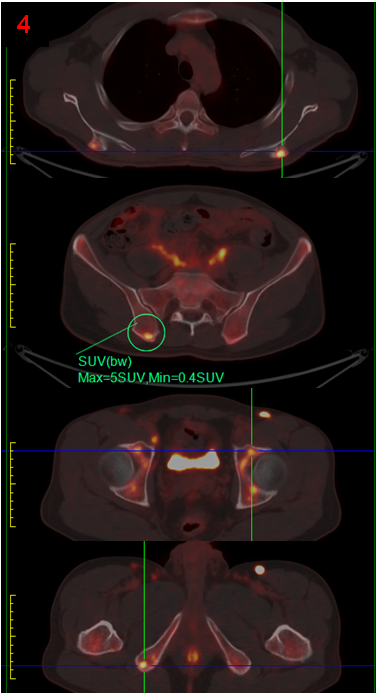

完善PET/CT檢查,示頸胸腹盆多處淋巴結或軟組織、右側腎上腺、腹膜(圖3),以及全身多處骨骼/骨髓(圖4)異常代謝,考慮淋巴瘤,建議病理檢查。

參考PET/CT結果,對代謝最高的右腹股溝區(qū)淋巴結進行了活檢,并完善了骨髓穿刺活檢病理檢查,最終證實為濾泡性淋巴瘤侵犯骨髓。

PET/CT顯示除腹膜后病變外,頸胸腹盆部存在多發(fā)高代謝淋巴結,以及多處骨骼/骨髓代謝異常,同時胰腺并未表現(xiàn)出異常高代謝,最后綜合考慮為淋巴瘤,并得到病理證實。

本案例充分體現(xiàn)了PET/CT的優(yōu)勢,一是全身顯像,在圖像上“一目了然”地了解全身所有臟器組織的葡萄糖代謝情況,為診斷提供新的思路;二是代謝顯像,直接反映了組織器官的功能狀態(tài),為診斷提供了份量極重的砝碼;尤其在淋巴瘤的診斷中,代謝程度最高的病灶意味著活躍程度最高,對其活檢結果最準確、可靠。